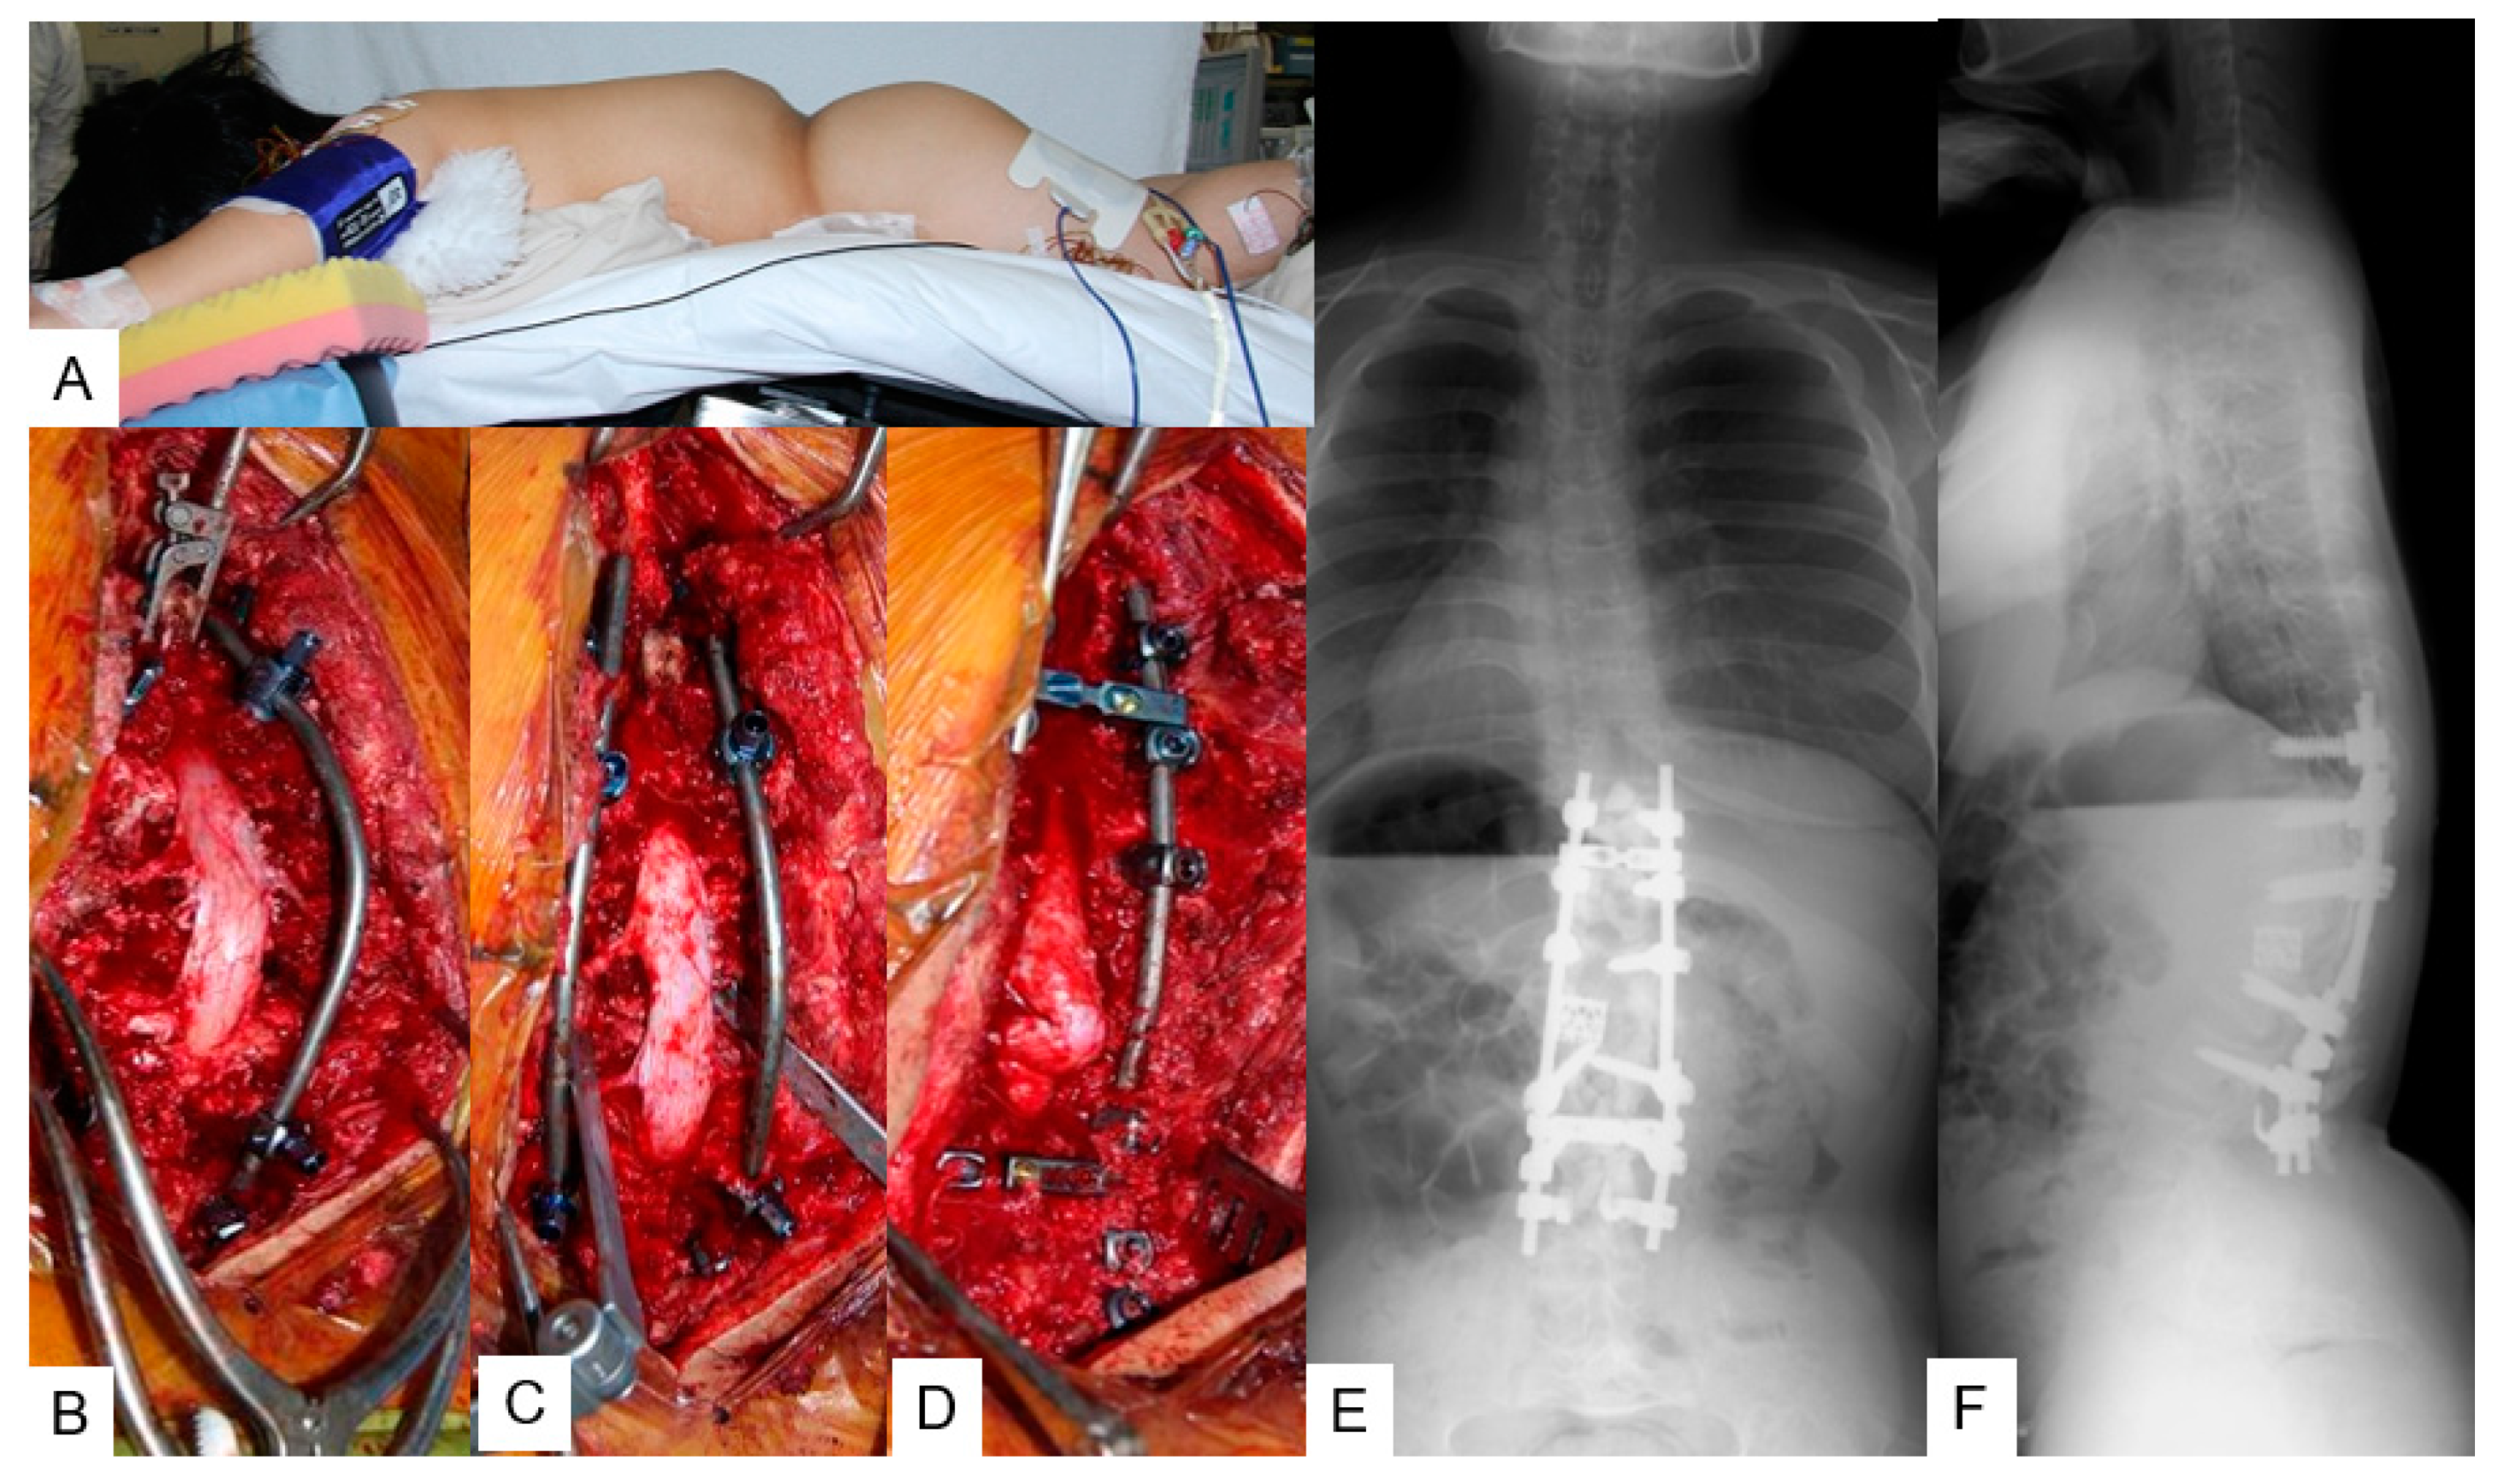

3.1. Case 1—16-Year-Old Girl, Achondroplasia, Thoracolumbar Kyphosis 126°

3.1.4. Surgery

3.1.5. Postoperative Imaging

| 1 | 7 | 11 | 10 | 126 | 14 | 89% | T9-L3 | T12,L1 | SSI (day 10) |